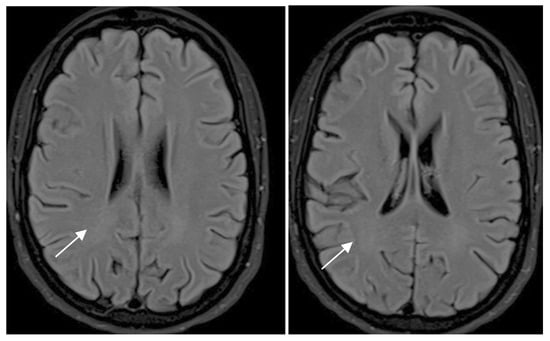

| White Matter Lesions | Rating Scale for MRI |

|---|---|

| 0 | No lesions |

| 1 | Focal lesions |

| 2 | Beginning confluence |

| 3 | Diffuse involvement of entire region, with or without involvement of U fibers |